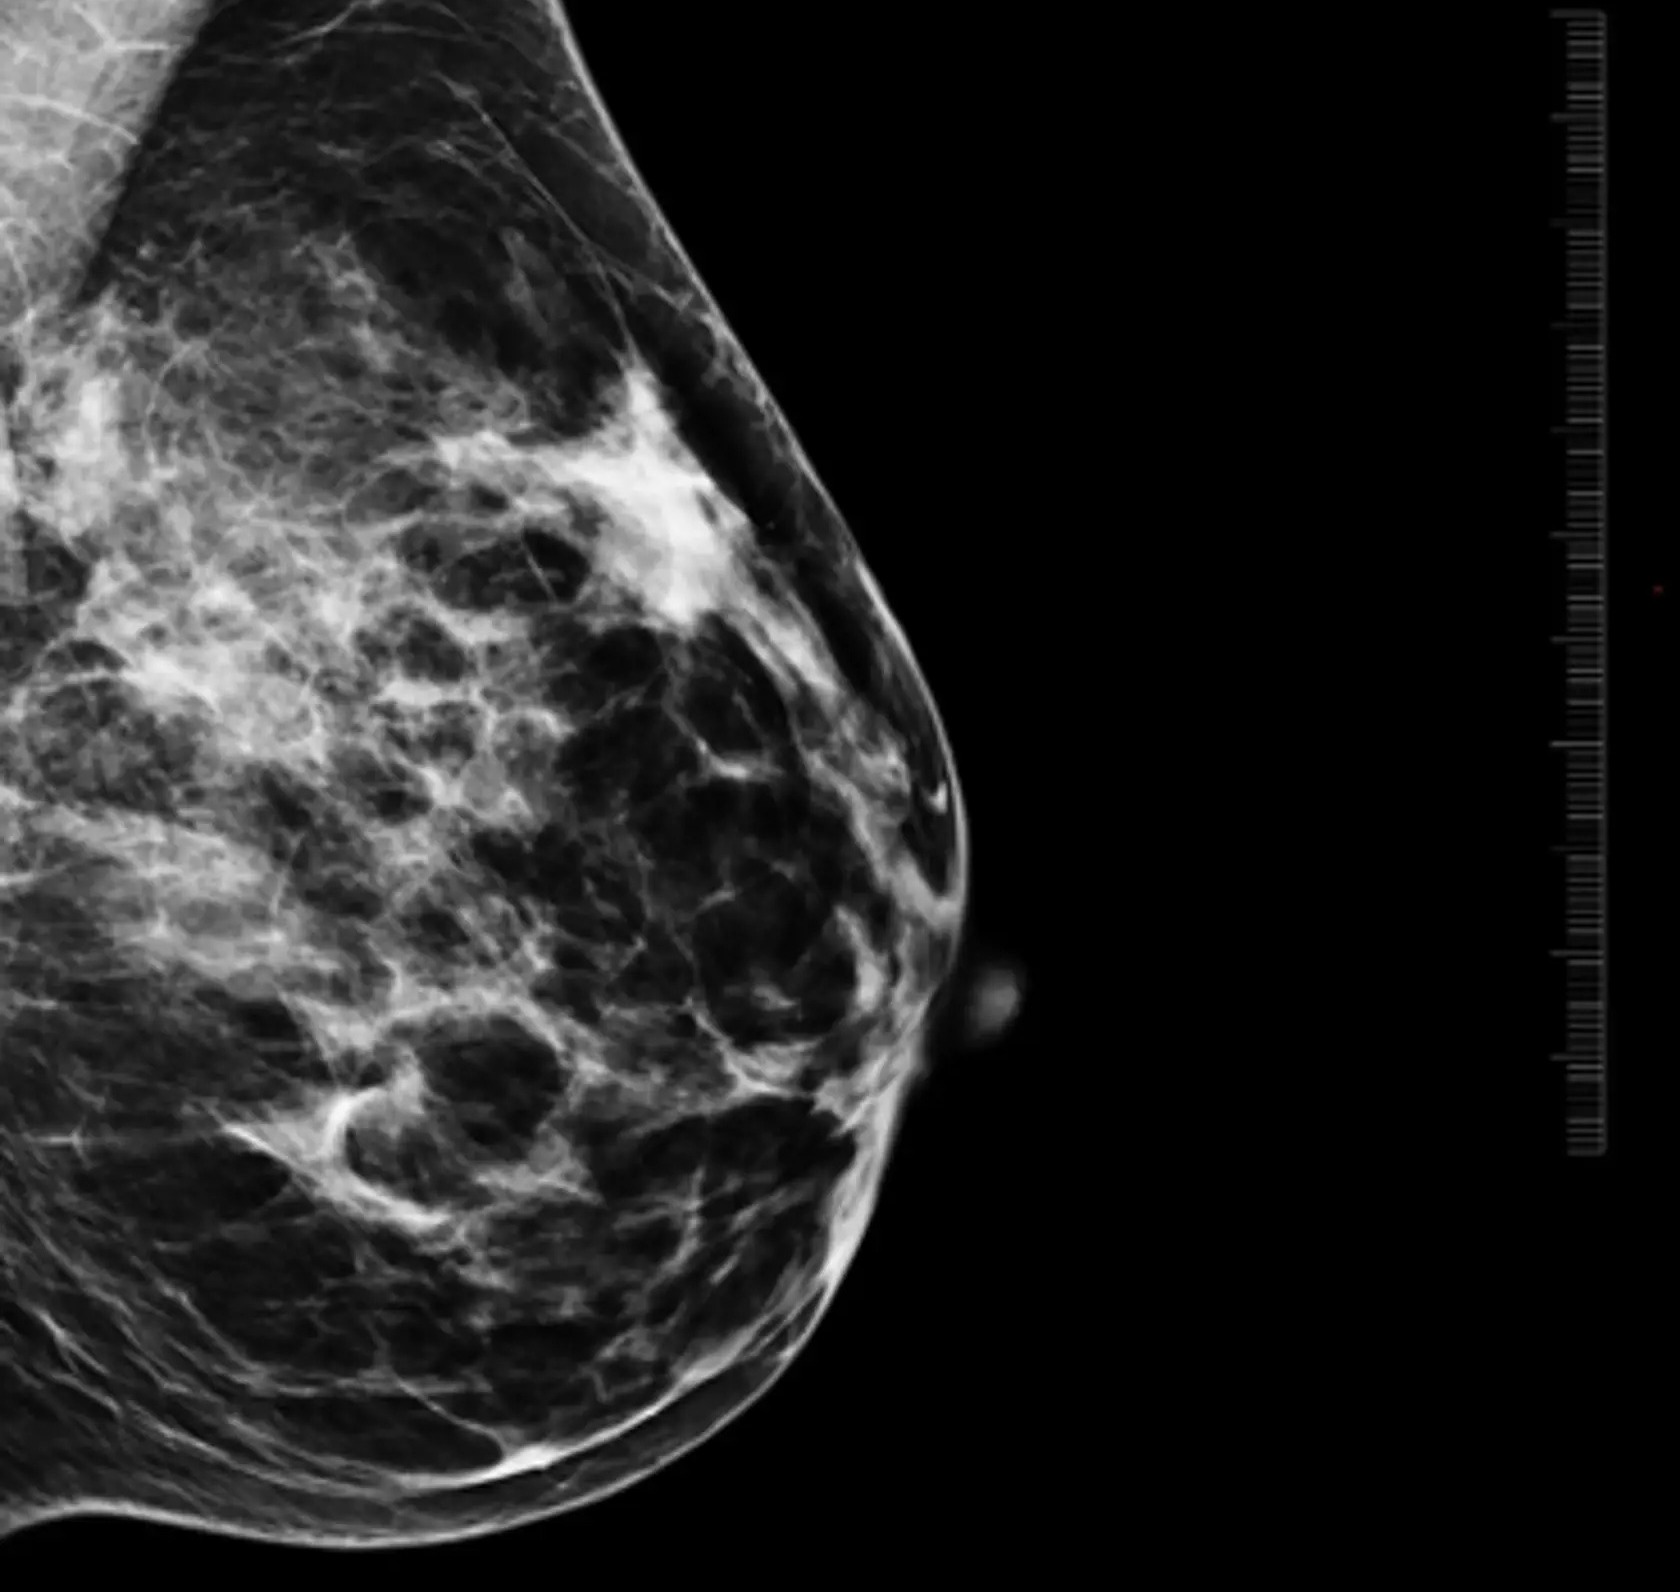

Mikrokalcifikáty sú drobné usadeniny vápnika v tkanive prsníka, ktoré sa pomerne často objavujú pri mamografickom vyšetrení. Vyskytujú sa približne v 85 percentách prípadov a častejšie sa objavujú s pribúdajúcim vekom.

Lekári pri hodnotení mikrokalcifikátov sledujú viacero znakov, napríklad ich veľkosť, tvar, hustotu, rozloženie v prsníku či to, ako sa menia v čase. Práve tieto informácie pomáhajú určiť, či ide o bežný a neškodný nález, alebo o zmenu, ktorú treba podrobnejšie vyšetriť.

„Mikrokalcifikáty môžu byť v úplne skorom štádiu viditeľné len na mamografii, často ide o zmeny veľké len niekoľko milimetrov. Práve preto je mamografické vyšetrenie také dôležité a nenahraditeľné. Väčšie zmeny môžu byť neskôr viditeľné aj na ultrazvuku,“

vysvetľuje MUDr. Alexandra Bieliková, lekárka rádiológie AGEL Mammacentra sv. Agáty.